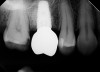

Due to the need for medical treatment for shoulder and neck issues, the patient was delayed in returning to the office for subsequent evaluation. At the 7-month postoperative appointment, the socket was assessed and a panoramic radiograph was taken to evaluate the bone at the planned implant site (Figure 1). The socket was filled with bone that was indistinguishable from the patient's native bone adjacent to the site. Insufficient height to place an implant was noted, which would require a crestal sinus lift prior to implant placement. A cone-beam computed tomography (CBCT) scan was ordered for planning purposes. Planning software was used to properly position a 5.2 x 10 mm implant for placement into the edentulous site, confirming that some elevation of the sinus would be required (Figure 2 and Figure 3). This data was used to order a surgical stent to guide implant placement (Figure 4).